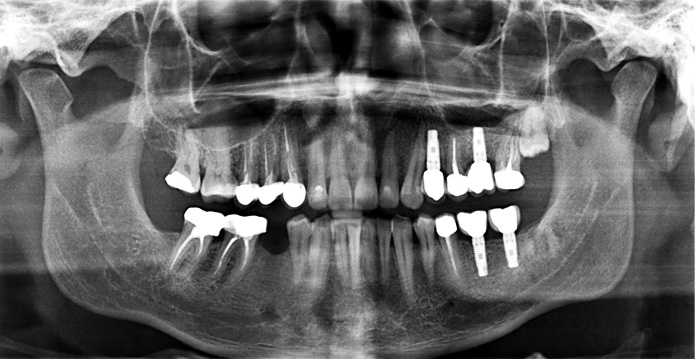

환자명 : 이OO

2025.05.26 업데이트

수술 후 촬영일자 : 2025.03.07